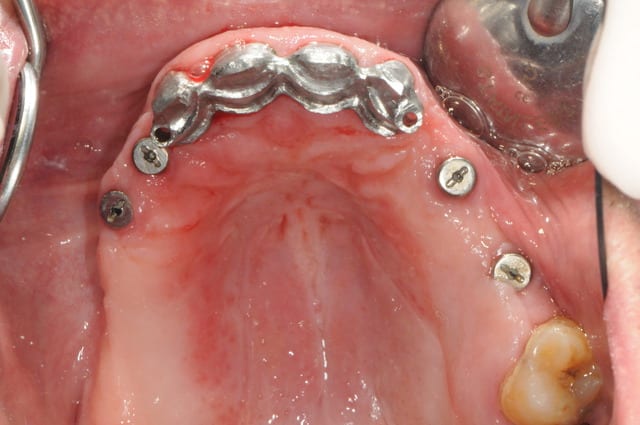

si ça peux alimenter ta réflexion...

manque d'intelligence de ma part j'ai pas fait de photo du cas au tout départ. mais la première photo devrait vous donner une idée du reste...

la suite c'est pose 4 implants, ceramique, stellite sur locators (beaucoup moins couteux qu'une barre et plus facile à nettoyer)